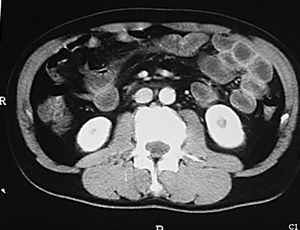

Al nivel de íleon terminal el espasmo justifica el signo de "la cuerda" (fig. 6). En relación no sólo con el espasmo, sino con una proliferación fibroadiposa del mesenterio aparece el signo del "asa orgullosa" en el estudio con bario, cuyo sustrato fisiopatológico ilustra la TC (fig. 7).

Fig. 6.--Enfermedad de Crohn, fase activa inflamatoria. (A) En el tránsito baritado: signo de "la cuerda" a nivel del íleon terminal. (B) La correlación en tomografía computarizada (TC) muestra engrosamiento mural, hiperemia y estratificación.

Fig. 7.--Enfermedad de Crohn, fase activa inflamatoria. (A) Signo del "asa orgullosa" en el tránsito intestinal. (B) Correlación tomodensitométrica: separación del asa intestinal del resto en relación con proceso inflamatorio de la grasa mesentérica.

Los hallazgos en la TC y la RM sugestivos de EC en fase activa son la hiperemia, característica de un proceso inflamatorio y la estratificación de la pared intestinal (fig. 8). El concepto de hiperemia que depende de la prominencia, tortuosidad y dila-tación de los vasa recta, se traduce por el signo del "peine" (fig. 9), descrito por Meyers y McGuire16 en estudios tomodensitométricos de pacientes en fase activa de la EC. Si bien no es un signo patognomónico de la EC, la hiperemia a nivel de las asas intestinales es marcador de actividad17. La estratificación de la pared intestinal justifica un aspecto en "diana" (fig. 3B) con una zona de alto valor de atenuación interna que corresponde a la mucosa, otra zona también de alto valor de atenuación periférica que corresponde a la muscular-serosa y una zona intermedia entre ambas, de menor valor de atenuación que corresponde a la submucosa edematosa en relación con la ectasia linfática12.